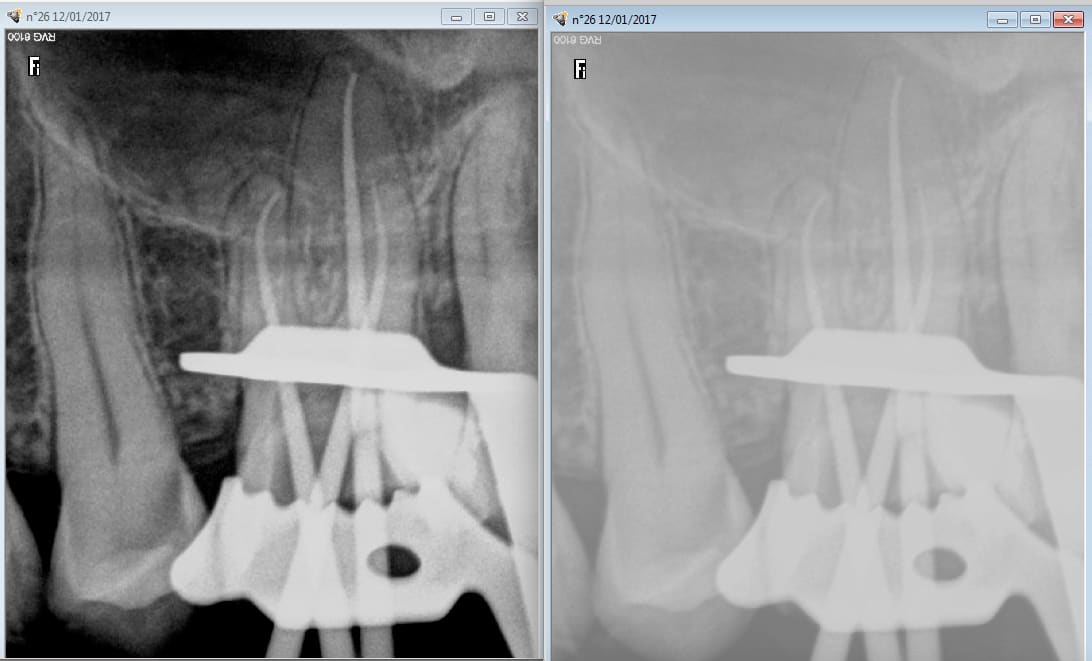

pis tiens un contre exemple , je ne suis pas chicot , j'ai pas tout ton matériel , je ne condense rien , ni à chaud ,ni à froid et pourtant ça sort pas mal !!! Comme quoi faut pas se fier aux photos , on peut tout faire avec ....

T'as quel capteur radio et avec quel logiciel? as-tu modifié des parametres? tu utilises quel ciment?

RVG trophy , ciment : Acroseal de SEPTODONT ,je crois que Chicot a une trophy aussi ...

Ah oui le logiciel y fait beaucoup parce que avec un même capteur et une mise à jour logiciel j'ai vraiment vu la différence de netteté !

Ouais , vais faire ça aussi comme chicot ! Pour la petite histoire de cette dent , gamine de 14 ans chez qui un jeune confrère a voulu faire un composite ... qui a mal tourné ! douleurs mais il n'a rien voulu savoir et les parents me l'ont amené .... Heureusement qu'ils n'ont pas attendu trop longtemps ....: bon , à sa décharge , faut dire que la gamine est ch ..pénible !